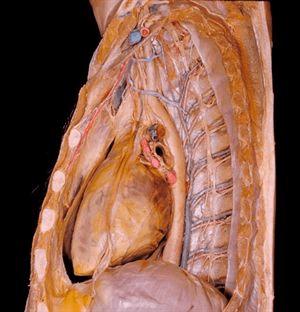

9.这个胸腔纵隔膜(位于肺之间的一个重要的胸腔隔膜)覆盖心脏。与右心室直接相连的血管是大动脉,它是人体内最大的动脉。在大动脉右边是一组血管(一根动脉和两根伴生静脉),它们在肋骨间穿行,将血液运输到全身各处。通过这张图,大家可以看到膈神经(将呼吸命令传输给横膈膜)垂直穿过心脏。